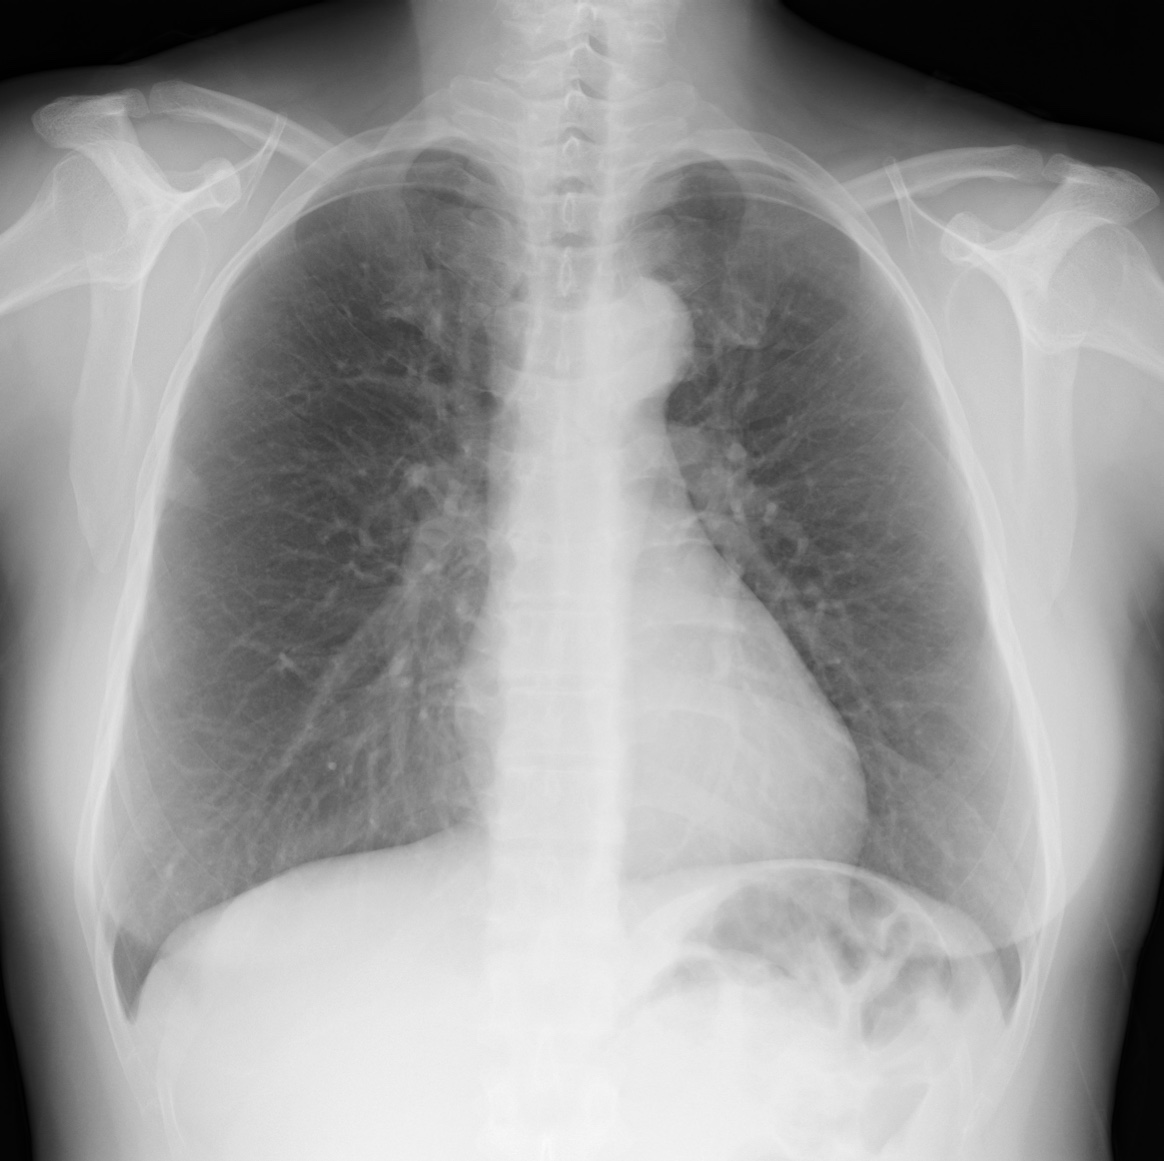

Bone Suppression Image processing technology uses advanced algorithms to attenuate the signals of the anterior ribs, posterior ribs, and clavicles of chest images, based on a proprietary chest X-ray image database.

By visualizing the "attenuated images of the clavicle / ribs", the visibility of lesions overlapping the bones in the lung fields is improved, and this strongly supports the diagnosis of chest.

- Provide a soft tissue-like image as below without any additional dose and equipment